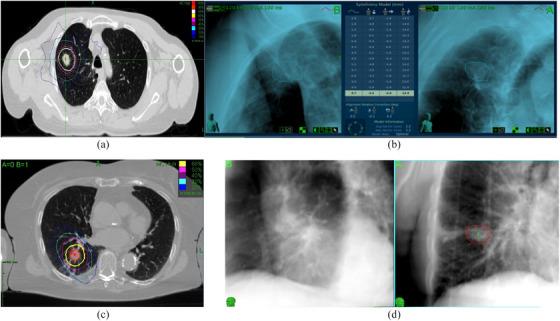

AAPM task group report 135.B: Quality assurance for robotic radiosurgery.

AAPM Task Group Report 135.B covers new technology components that have been added to an established radiosurgery platform and updates the components that were not well covered in the previous report. Considering the current state of the platform, this task group (TG) is a combination of a foundational task group to establish the basis for new processes/technology and an educational task group updating guidelines on the established components of the platform. Because the technology discussed in this document has a relatively small user base compared to C-arm isocentric linacs, the authors chose to emphasize the educational components to assist medical physicists who are new to the technology and have not had the opportunity to receive in-depth vendor training at the time of reading this report. The TG has developed codes of practice, introduced QA, and developed guidelines which are generally expected to become enduring practice. This report makes prescriptive recommendations as there has not been enough longitudinal experience with some of the new technical components to develop a data-based risk analysis.

美国医学物理师协会任务组报告135.B涵盖了已添加到既定放射外科平台的新技术组件,并更新了上一份报告中未充分涵盖的组件。考虑到该平台的当前状态,本任务组(TG)是一个基础任务组与一个教育任务组的组合,基础任务组为新流程/技术奠定基础,教育任务组更新该平台既定组件的指南。由于与C型臂等中心直线加速器相比,本文档中讨论的技术用户基数相对较小,作者选择强调教育组件,以帮助刚接触该技术且在阅读本报告时尚未获得深入供应商培训机会的医学物理师。该任务组制定了操作规范,引入了质量保证,并制定了通常有望成为持久做法的指南。由于一些新技术组件缺乏足够的长期经验来开展基于数据的风险分析,本报告提出了规范性建议。